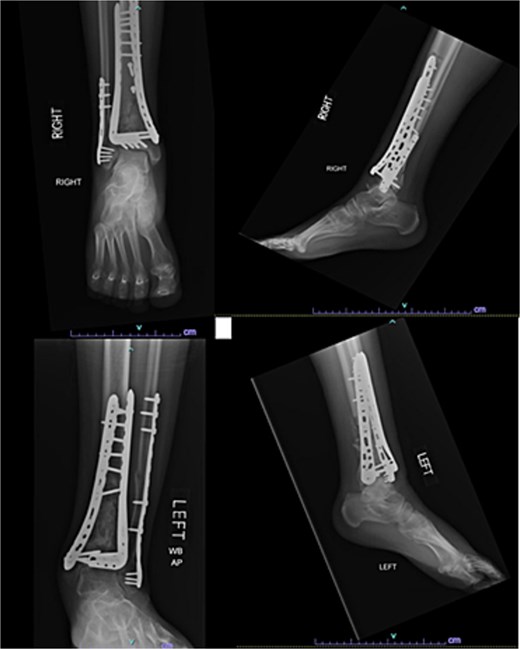

A 57-year-old male with a body mass index (BMI) of 48.7 kg/m2 and multiple comorbidities, including asthma, coronary artery disease, hypertension, hyperlipidemia, ischemic cardiomyopathy, obstructive sleep apnea, and hypothyroidism, following a motor vehicle collision when he lost control of his vehicle due to a coughing spell. His injuries included bilateral pilon fractures (Fig. 1), a T2 superior endplate fracture, and bilateral pulmonary contusions. He initially presented to a regional hospital and was transferred to our facility 10 days after the injury.

Anterior-to-posterior (AP) radiographs of patient 1 obtained 10 days after injury, upon transfer to our facility, demonstrating bilateral pilon fractures.